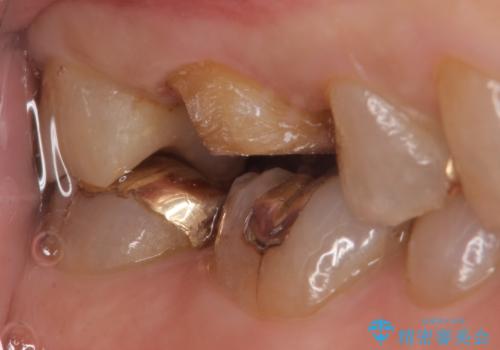

- 冷たいものがしみる右上の奥歯を治療して欲しいといらっしゃった方の症例です。

右上6,7の金歯を外したところ、虫歯が歯茎より深い位置まで進行していたため歯周外科を行いました。